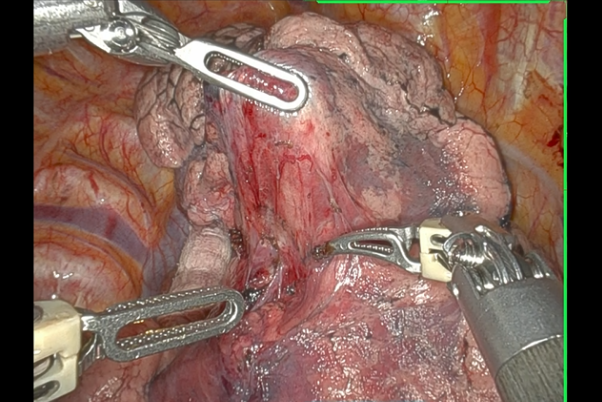

当院では、2022年から手術支援ロボット(ダヴィンチ)による肺がん手術を行っております。

手術は、図の如く3-4cmの皮膚切開1箇所と1-2cmの皮膚切開4箇所で行います。

医師はカメラで映し出された画像を見ながら、ロボットアームを操作して手術を行います。ロボットアームは医師の手と連動していて、狭い空間でも自分の手の如くに操作ができます。

医師が見るカメラの画像は、デジタルズーム機能で10倍まで拡大して見ることができます。また、操作する医師の手先の震えがロボットアームに伝わらないように、手ぶれを補正する機能もあり、緻密で正確な手術が可能になります。

| ▲肺がん手術の様子 |